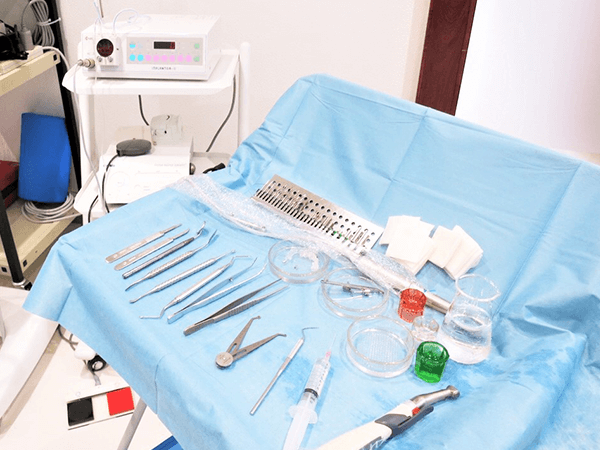

当院では毎週インプラント治療に係る外科処置を行っていますが、一つとして同じケースはありません。患者さまごとに、精確な診査・診断を踏まえ、科学的根拠に基づいた治療計画を立案し、多くの症例と経験に裏打ちされた技術で、精密なインプラント治療を行います。

インプラントには安定して永く使っていただける条件があり、当院では、その条件をしっかり満たせる治療計画を立てます。例えば、顎の骨量や歯ぐきの形もポイント。必要に応じて、骨量を増やす処置を行ったり、歯ぐきの形成を行ったりします。これらの処置には、技術も環境も有能なスタッフも必要ですが、当院でならそれが達成可能です。

3Dデータによる事前のシミュレーション

インプラント治療には、事前のシミュレーションが欠かせません。そして、シミュレーションのためにも精密な検査が不可欠なのです。当院では、CT撮影で口腔内の状況を確認するだけでなく、口腔内スキャナーを使用して口腔内データを取得。どの角度でインプラントを埋入するのがベストか、コンピュータ上で入念にシミュレーションします。このシミュレーションから模型を作製し、サージカルガイドを作製します。シミュレーション段階から精確には精確を期して、よりよいインプラント治療をご提供しています。